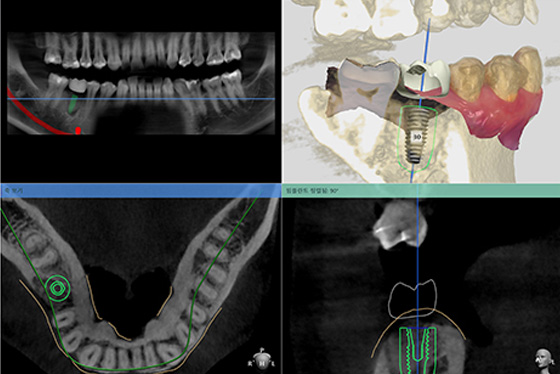

철저하고 정확한 준비

한 번 잘못 심어진 임플란트는 바로 잡기가 매우 어렵습니다. 솔트 치과는 수술 전 3D CT와 디지털 구강스캔 후 임플란트 식립 위치를 잡고, 수술 시 네비게이션 가이드로 안전하게 위치시킵니다.

최소절개와 빠른 회복

디지털 X-ray 장비를 통해 환자의 잇몸 뼈를 정확히 예측하여 최소한의 절개와 간결한 수술로 빠른 회복이 가능합니다.